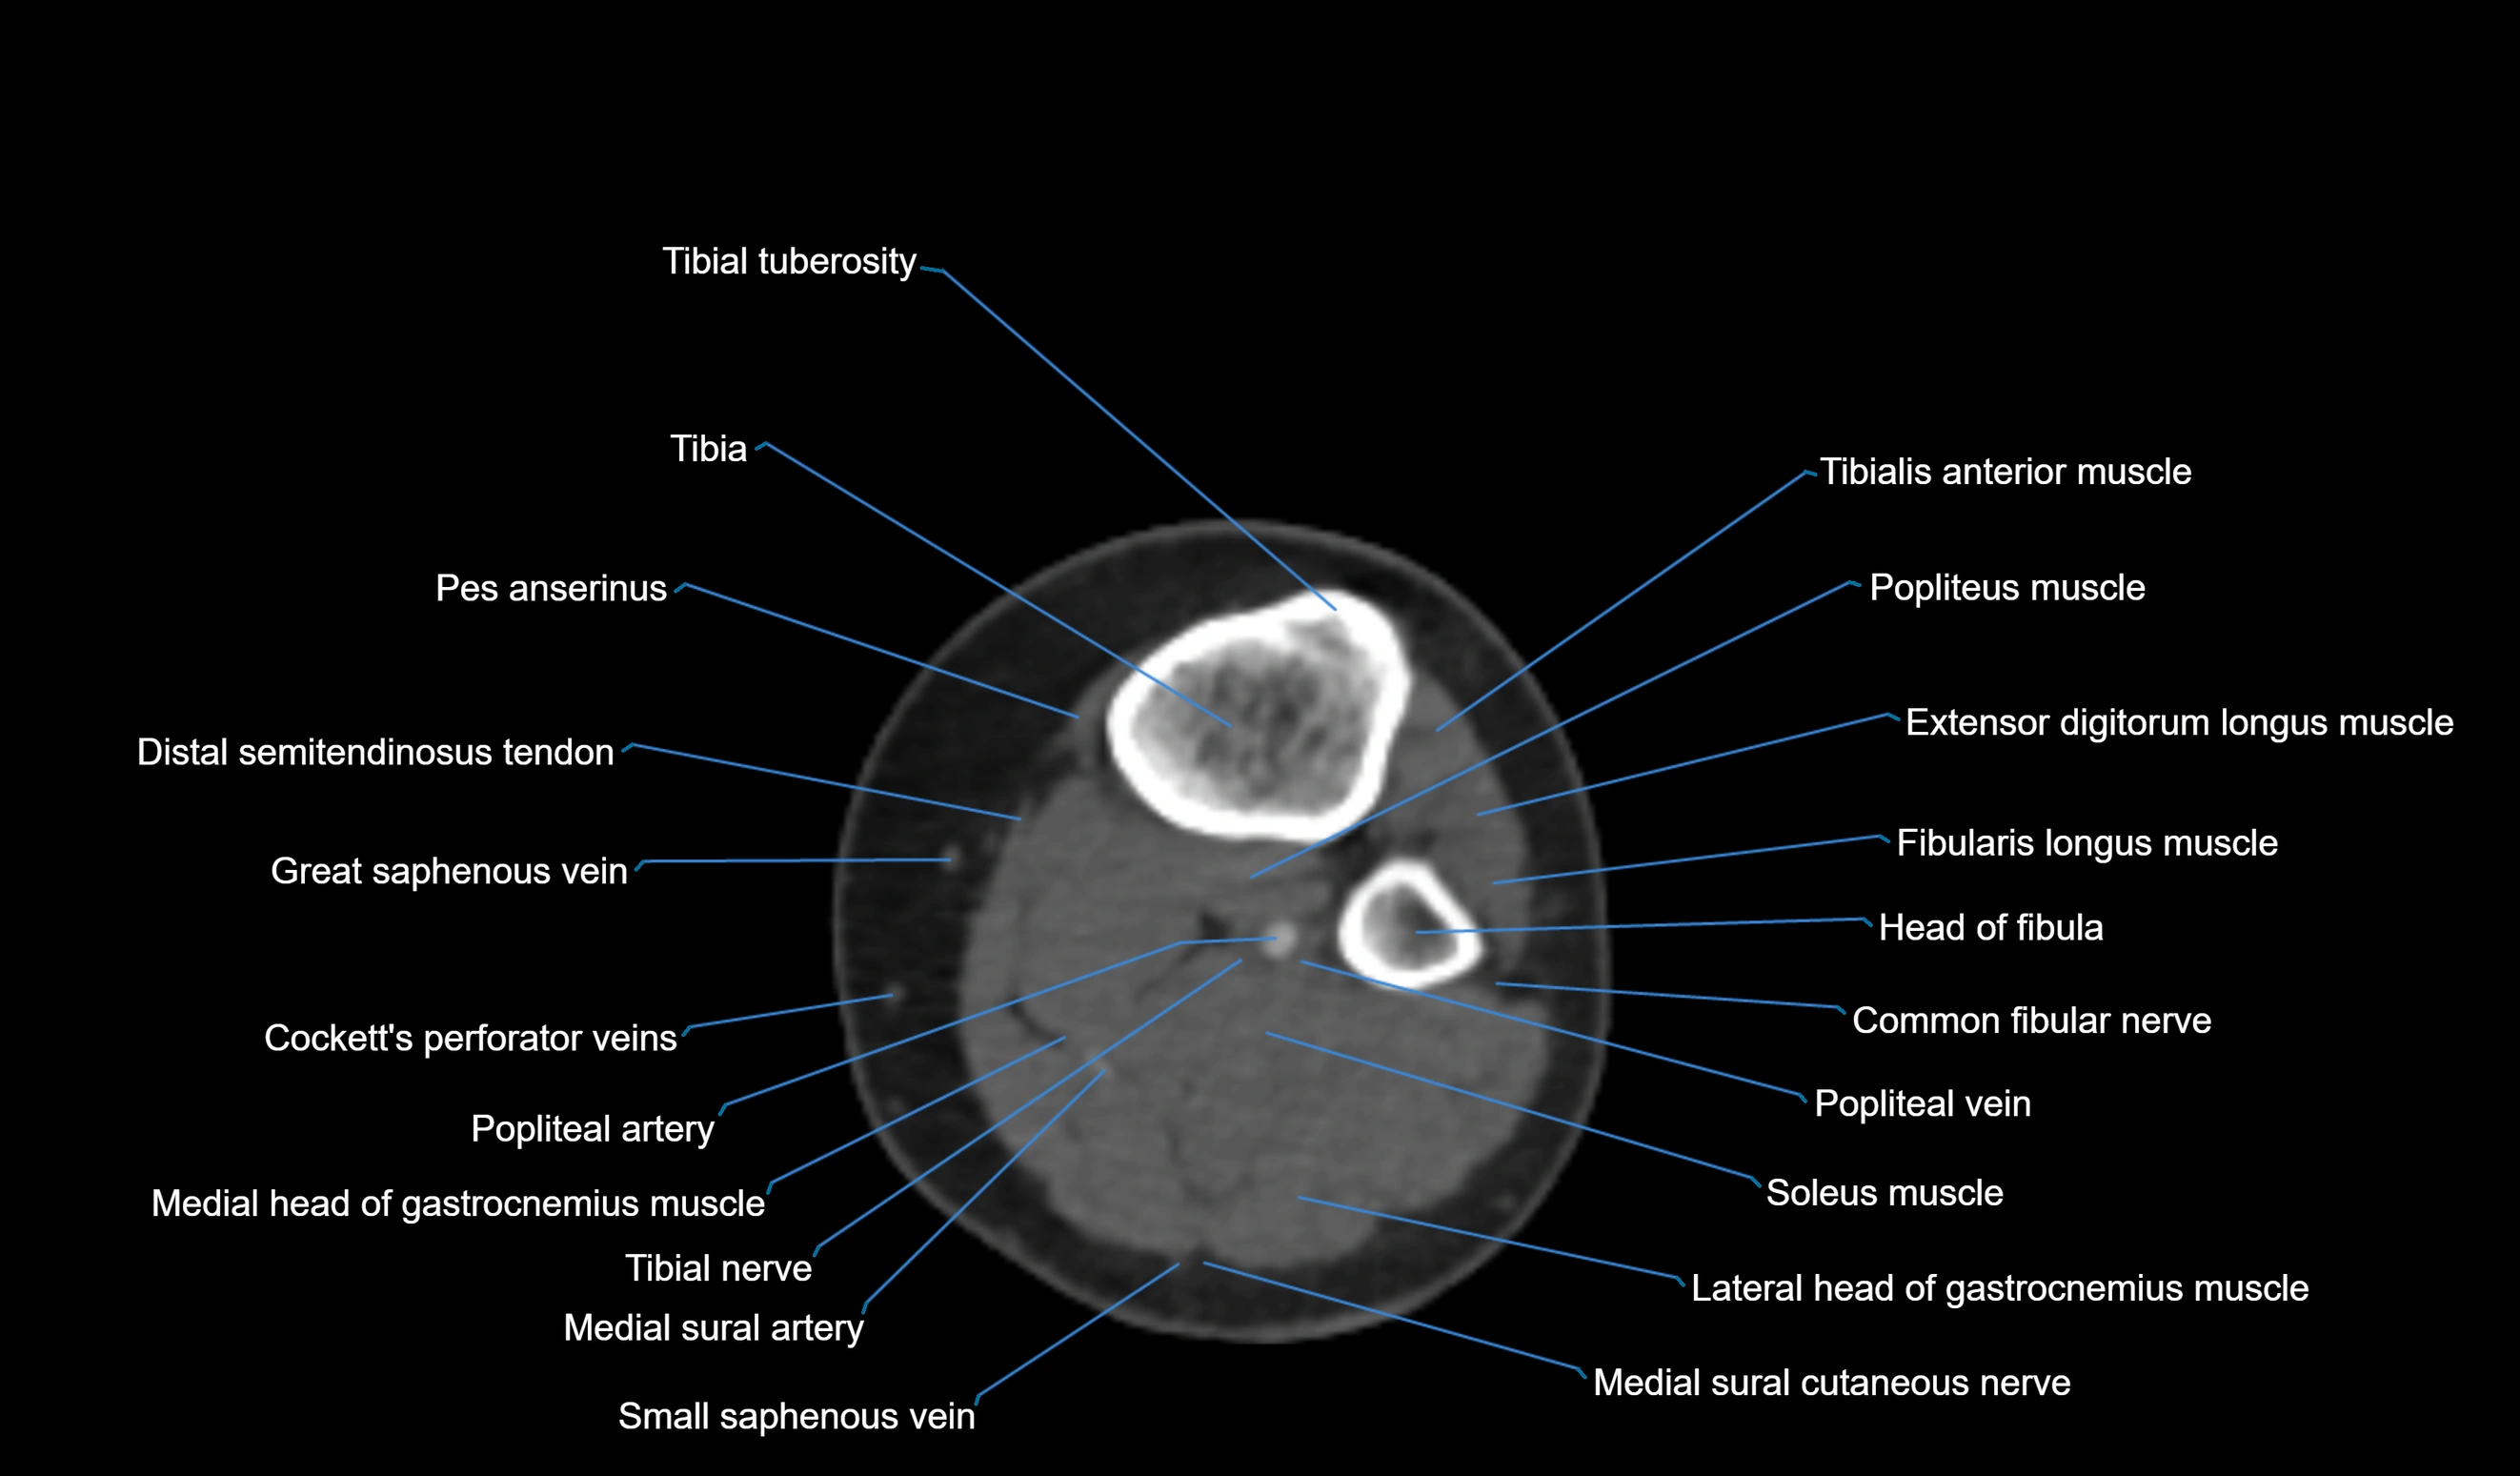

CT VRT 3D image

CT image